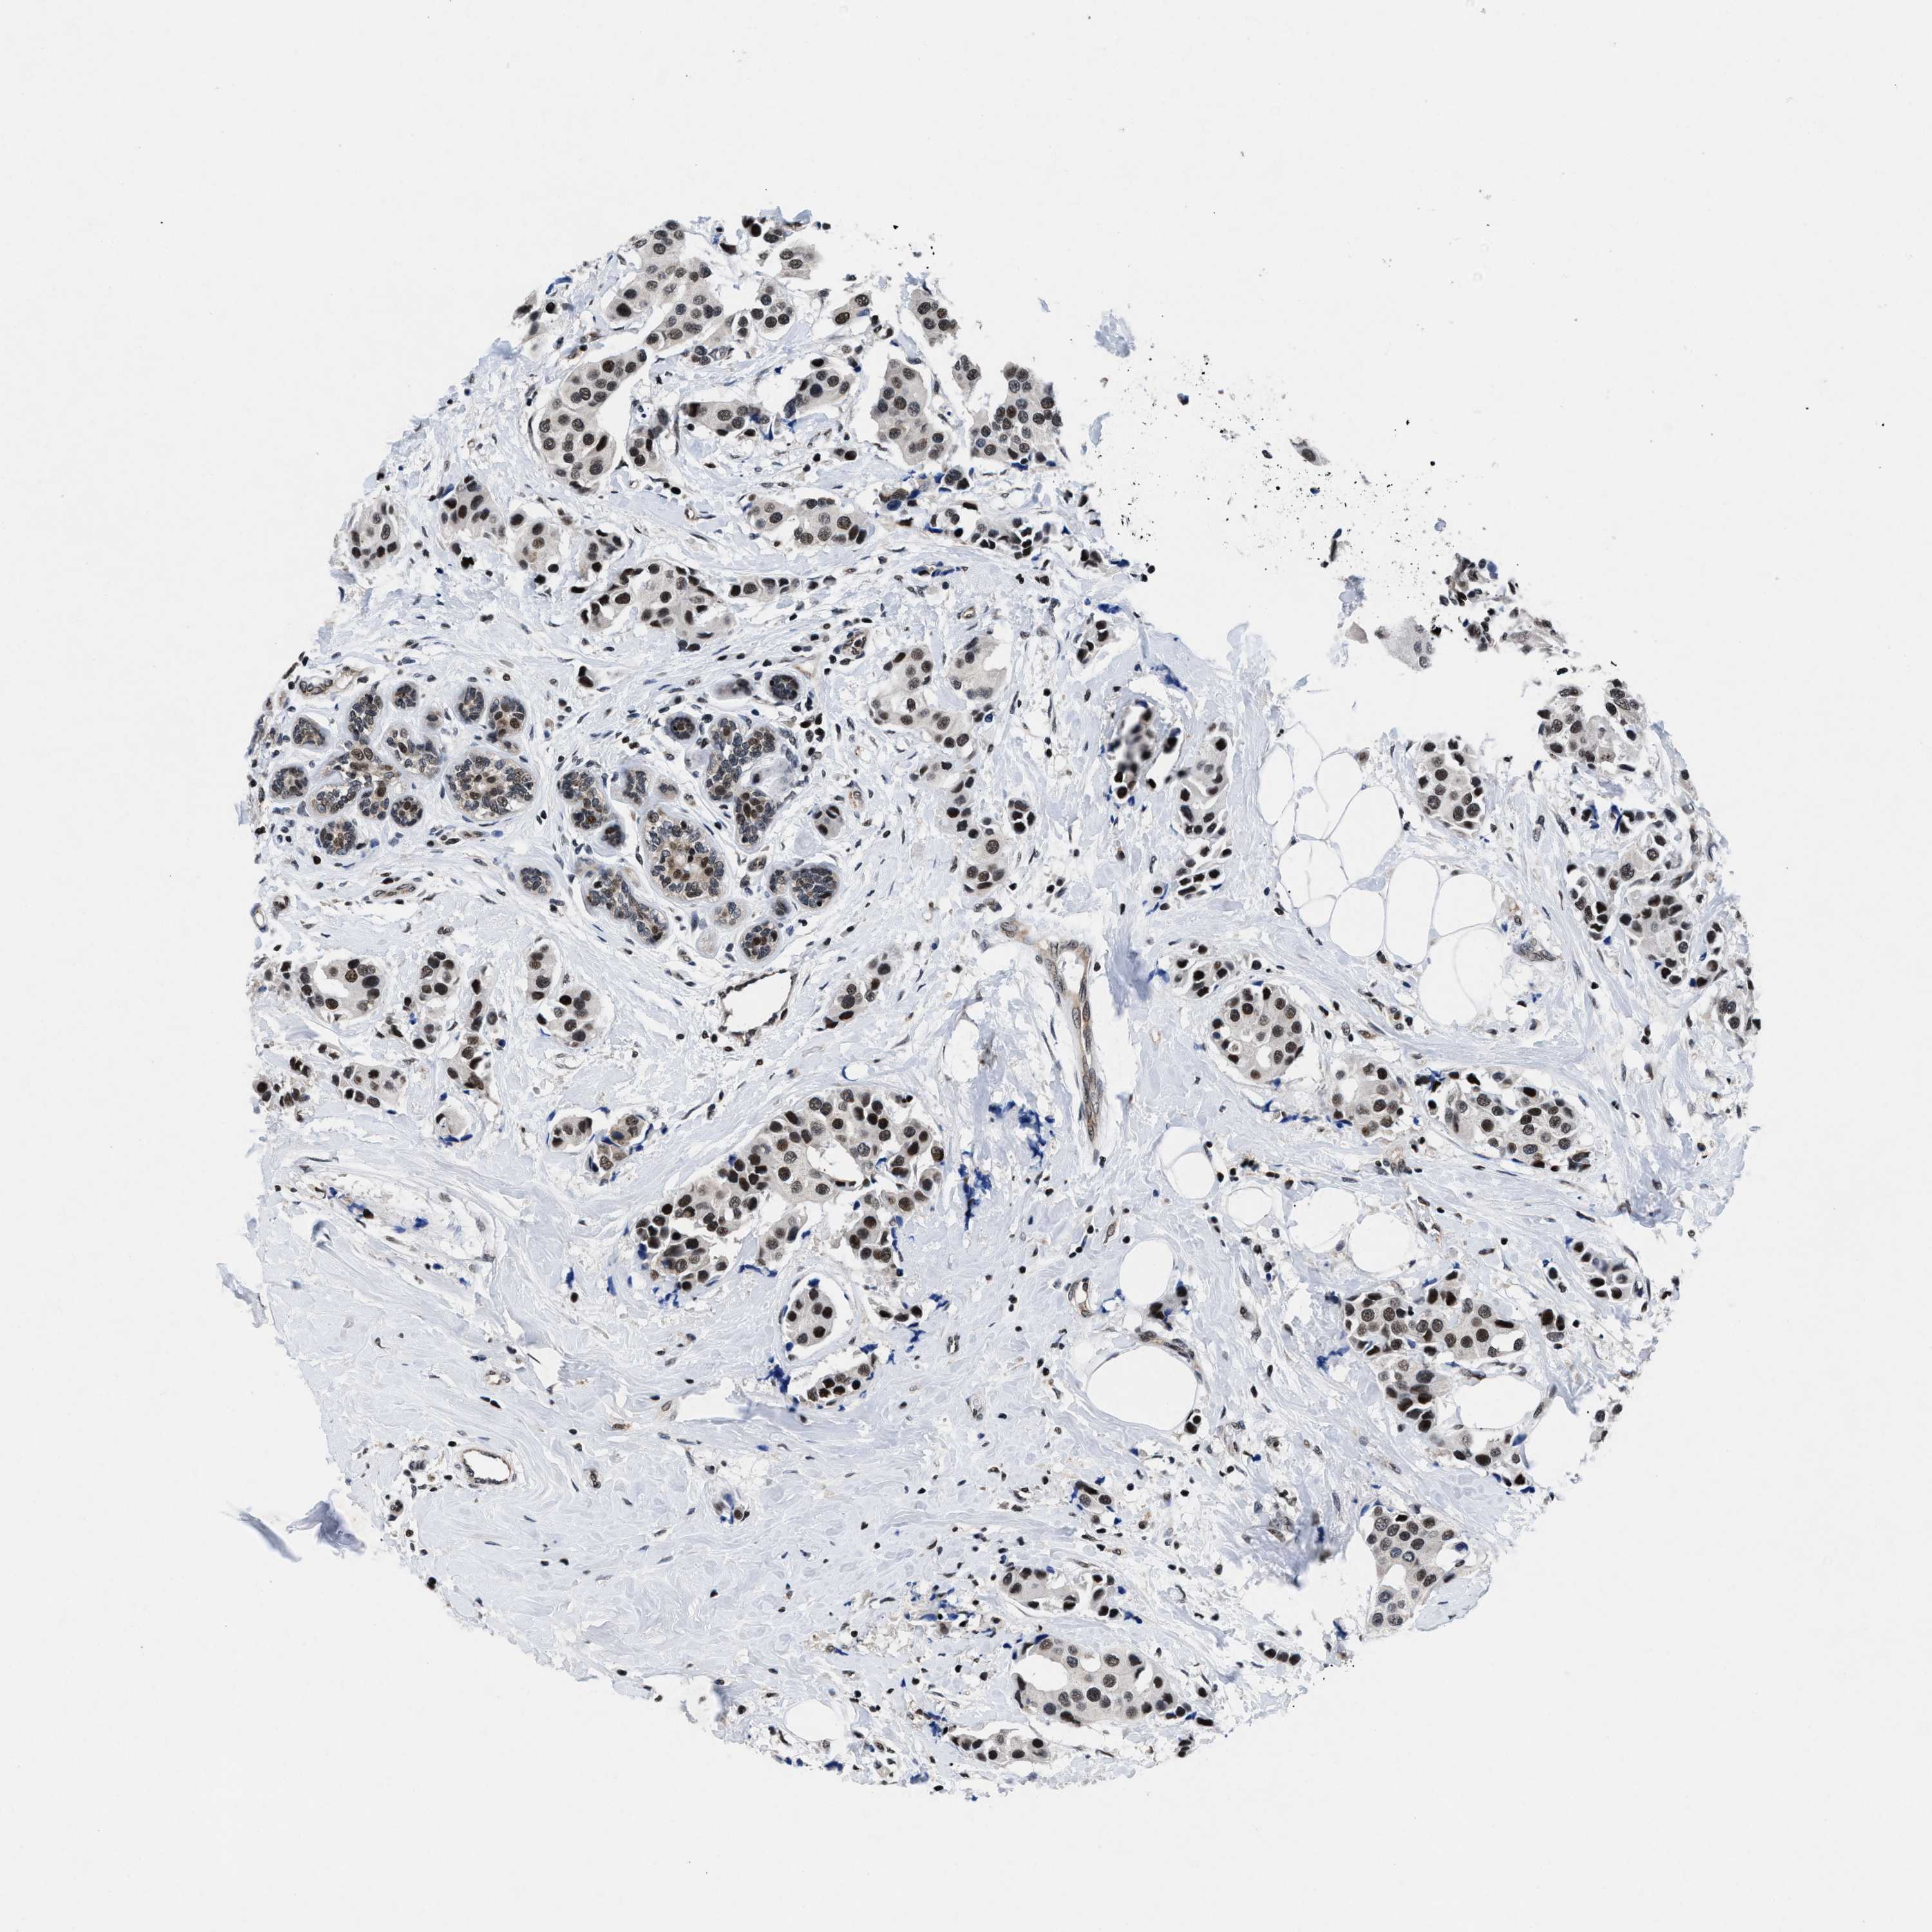

CANCER BREAST CANCER Show tissue menu

BRCA TCGA BRCA VALIDATION PROTEIN EXPRESSION

Breast cancer

Human cancer